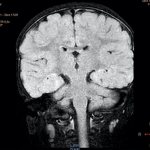

Диагностика Для определения рассеянного склероза врачи используют методы опроса и неврологического осмотра, а затем